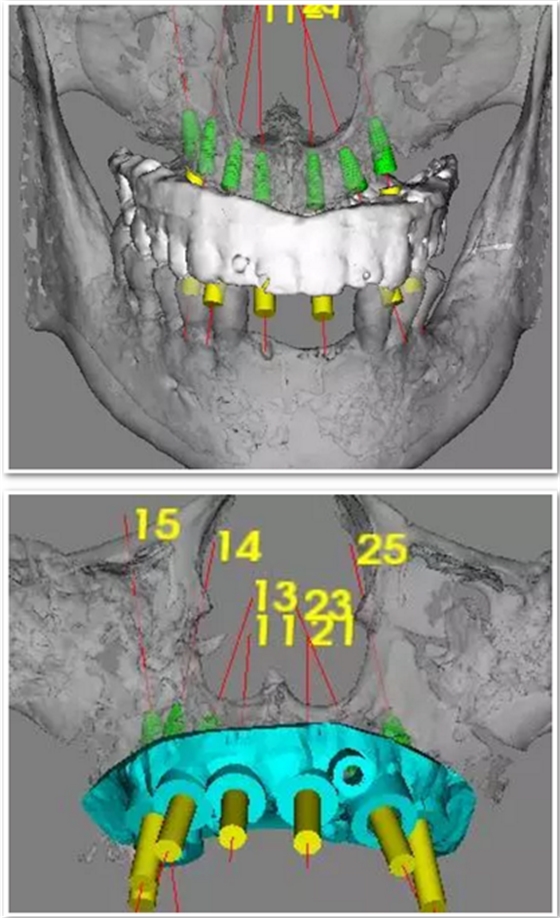

臨床手術(shù)

手術(shù)時,帶上導(dǎo)板,逐級備孔,在15和25的位置需要進(jìn)行內(nèi)提升,因此對于備孔深度的把控尤為重要,導(dǎo)板的作用得到了重大發(fā)揮。

去掉導(dǎo)板,進(jìn)行上頜竇內(nèi)提升,填入骨粉,植入種植體。